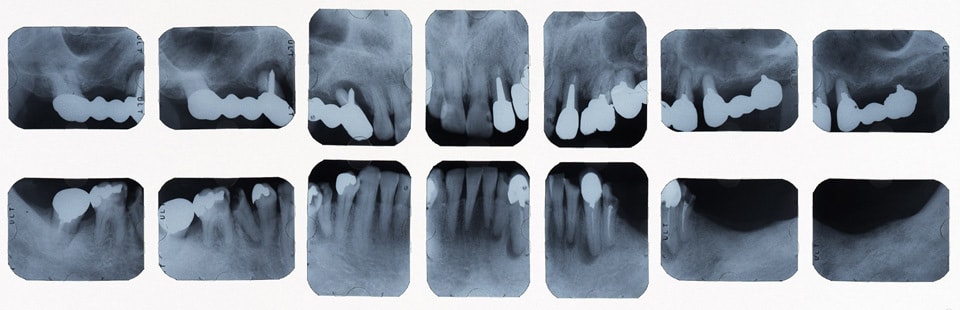

治療前レントゲン

奥歯をインプラントにて治療し、よく噛めるようにしました。また、虫歯や歯の根の治療のやり直しを行いセラミックにて審美的に修復しました。